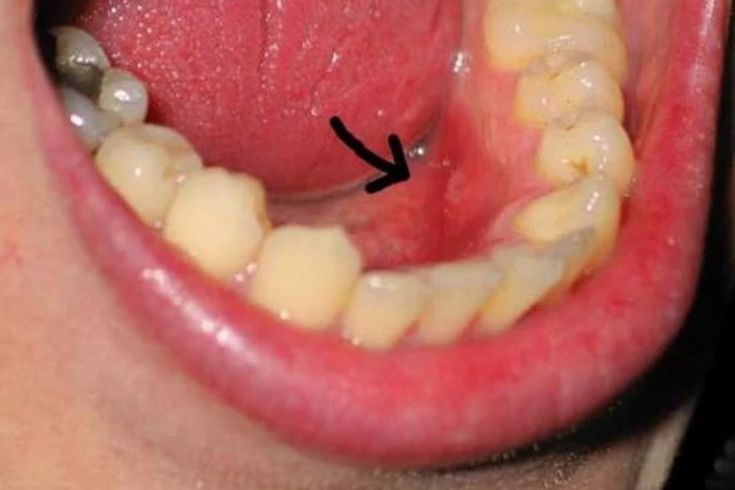

Xuất hiện mủ giữa răng và nướu: Khi ấn vào vùng nướu bị viêm, bạn có thể thấy một ít dịch mủ màu trắng hoặc vàng chảy ra. Đây là dấu hiệu của tình trạng nhiễm trùng đang hoạt động.

Áp-xe nha chu: Là một túi mủ hình thành trong túi nha chu do nhiễm trùng cấp tính, gây sưng, đau dữ dội và có thể cần can thiệp khẩn cấp.